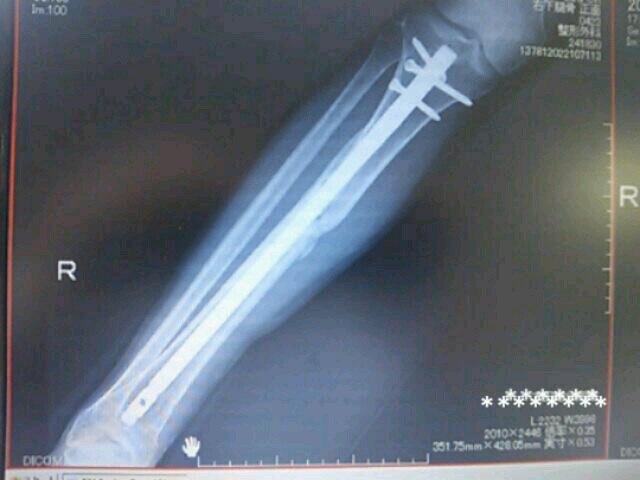

持ち帰りはできないけど

センセが実物を見せてくれました

ゴールド!

金メッキ?

抜釘した同室の彼女の髄内釘を見せてもらいました

意外と細いシルバーのアルミみたいな棒でした

R病院のKさんのチタンの輝きはありませんでした

本当にチタン(;ーー)?

彼女は2本ビス

自分は3本ビス

強度の違いだそうです

自分は骨頭にヒビも入ってたしね

彼女の色と違いますが?

右用?左用?

ていうか色なんてどうでもいいの?

バージョンが違うんですか

「そうそうバージョンが違うんだよ」

センセったらいい加減なこといって

詳しく知らないのね